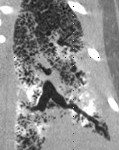

Chest computed tomography (CT) of patient with PAM showing symmetrical lower lobe predominant micronodular calcifications along bronchovascular bundles and interlobular septa.

The PAM mouse model study was inspired by a patient seen by Dr. McCormack in 2011 at UC Medical Center. The woman had been diagnosed with PAM as a child in Jordan and developed exertional dyspnea at the age of 54, a typical pattern for PAM. Chest examination revealed bibasilar crackles, pulmonary function tests revealed mild restriction and reduced diffusing capacity, and a six-minute-walk test revealed normal exercise capacity with mild exertional desaturation to 88%.1 Chest X-ray showed fine hyper dense lower lung zone nodular opacities, and computed tomography of the chest showed symmetrical lower lobe predominant micronodular calcifications along bronchovascular bundles and interlobular septal thickening, findings pathognomonic for PAM.1